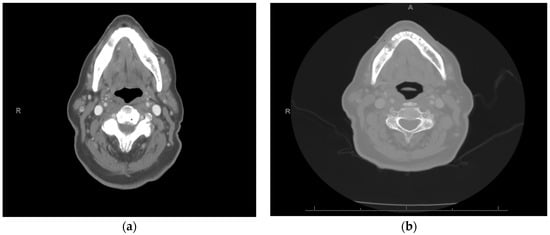

An 82-year-old male with an ECOG classification of 0 presented for evaluation of a mild to moderately painful recurrent mandibular gingival carcinoma. He had previously been treated with a combination of surgery and radiation therapy for a cT2N0 squamous-cell carcinoma of the right mandible. Three years later, he presented with a recurrence in the right mandibular gingiva, specifically at the level of the premolars (Figure 5). A biopsy confirmed the recurrence as rT2N0 squamous-cell carcinoma. Pretreatment MRI revealed swelling in the right gingiva buccal region of the mandible (Figure 6a). Additionally, there was evidence of cortical erosion in the right mandibular premolar region, indicating superficial invasion of the recurrent malignancy. Notably, there was no cervical adenopathy.

The patient was presented with treatment options, including curative surgical resection, which would have required mandibulectomy and a free fibula flap. Also, he was offered systemic chemotherapy and possibly reirradiation. However, the patient declined these options due to a desire to avoid mandibulectomy and further radiation treatment. Instead, the patient expressed interest in immunotherapy. His CPS score was found to be 30%, and he commenced treatment with pembrolizumab, administered at a dosage of 200 mg every 3 weeks. After three months of single-agent pembrolizumab, there was a noticeable decrease in the prominence of the tumor previously located around the right mandibular premolar region, and there was no longer evidence of exophytic growth (Figure 7). A post-treatment MRI was completed which showed a reduction in the swelling along the anterior right gingivobuccal region and stability of the erosion of the alveolar/periodontal region, particularly medial to the first and second premolars, near the site of the tumor (Figure 6b). Clinical examination findings thus demonstrated a partial treatment response.

Figure 6. MRI shows (a) buccal thickening (red arrow) in site of carcinoma pretreatment and (b) interval decreased thickening (red arrow) of right buccal tissues post treatment.